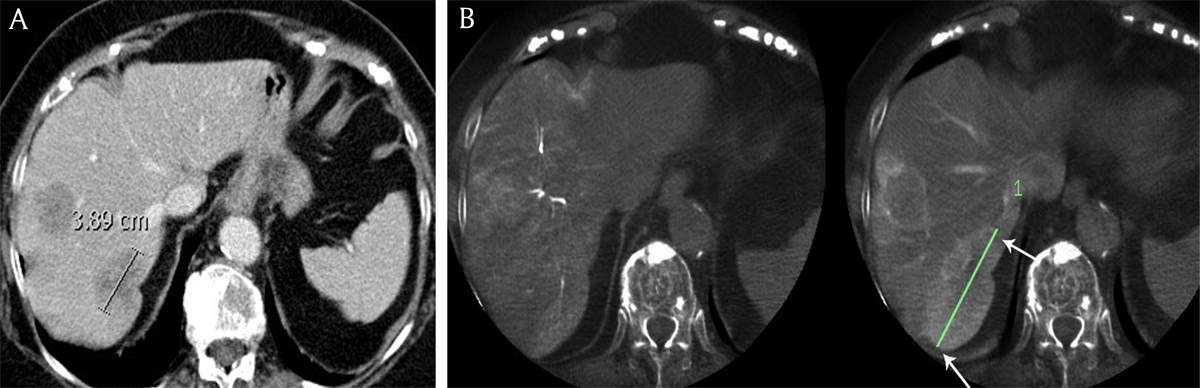

Tumor size. Tumors consistently appeared significantly larger on DP-CBCT than on CE-CT regardless of origin: breast: 57 ± 10mm versus 43 ± 8.5mm (p = 0.03) (Figure 3); colon: 57 ± 9.5mm versus 43 ± 8.3mm (p = 0.02); neuroendocrine: 56 ± 6.3mm versus 51 ± 5.8mm (p = 0.01) (Table 3 and Figure 4).

Figure 3

A) Contrast-enhanced computed tomography and B) cone beam computed tomography in an 81-year-old female patient with breast cancer liver metastases demonstrates the longest diameter of the largest metastasis (white arrows), measuring respectively 3.9 cm and 7.9 cm.